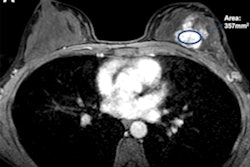

As an example, the researchers noted the results of a 39-year-old patient with hormone receptor-positive, HER2-negative breast cancer. They wrote that while CT at the initial staging of the thorax and abdomen gave suspicion of lymph node infiltration, conventional imaging couldn't clearly represent the tumor-infiltrated lymph node.